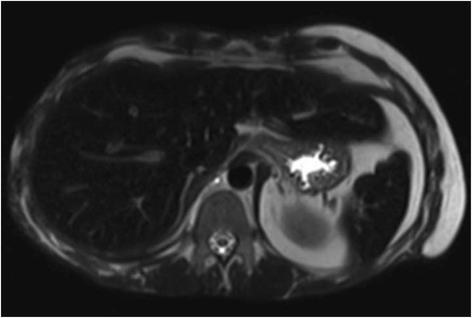

While in hospital, he had multiple zinc, selenium, and copper serum values in the low and normal ranges. However, he was noted to have elevated serum iron levels and an increased iron saturation index reaching 94 % (normal <60 %). His iron indices were followed throughout his stay as all values progressed to outside the normal limits (Table 1). Subsequent magnetic resonance imaging (MRI) of the abdomen verified the diagnosis of hemochromatosis by showing iron deposition in the liver and spleen (Fig. 1). A search for etiology revealed that in just less than 15 months, he had received 292 units of packed RBCs. He did not receive any exogenous administration of iron during his treatment course. With this information, it was thought that the increased iron saturation was due to a transfusional iron overload. Given his ethnicity and age in the presence of a clear alternative diagnosis, the clinical decision to forego genetic testing was made by the Internal Medicine and Hematology services. He had not manifested any typical signs or symptoms of secondary hemochromatosis. The Hematology service was consulted, and as per protocol, he was started on twice weekly phlebotomies [7]. Due to pre-syncopal episodes, he was unable to tolerate this, and thus, phlebotomy was performed weekly.

There is a wide differential of potential causes to consider in patients presenting with iron overload. In this case, the MRI suggested a pattern of iron overload consistent with a secondary (i.e., non-hereditary) process. A review of secondary causes reveals that he did not receive parenteral iron during his stay, did not have a history of chronic anemia or liver disease prior, is not of African descent, and did not have any neurological dysfunction to suggest aceruloplasminemia. Based upon the quantity of RBC transfusions administered during his course, it appears this is the most likely diagnosis.